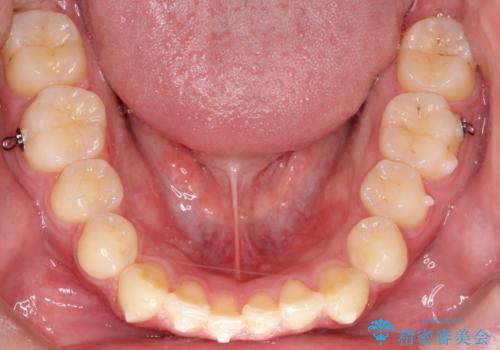

初診時の歯並びの状態としては、上下ともに前歯部の中等度以上のがたつき(叢生)があり、右の前歯が1本飛び出した状態でした。

抜歯は行わず上下顎ともに、主に歯列弓の拡大とディスキング(歯と歯の間に隙間を作る処置)を行い叢生を改善しました。

見た目、嚙み合わせ及び、治療期間や施術内容に大変ご満足いただきました。